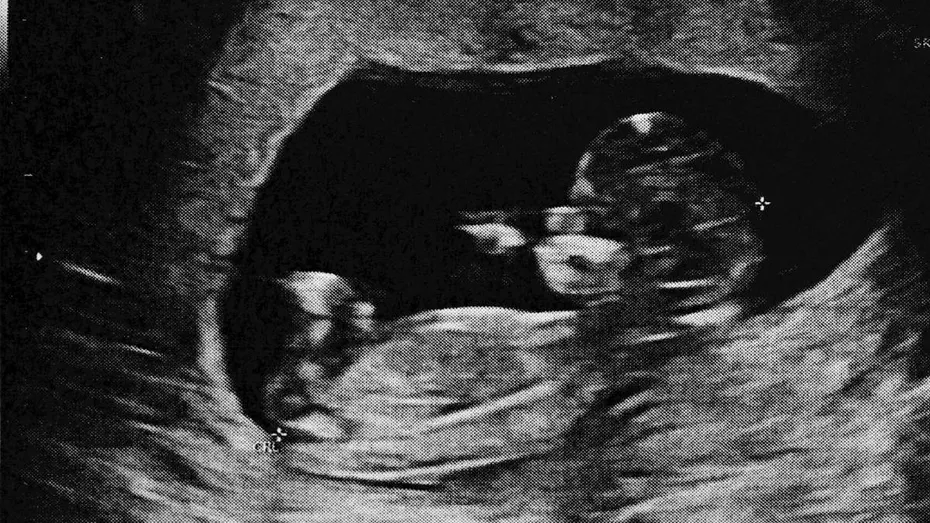

Termenul lithopedion provine din limba greacă, de la „litho”, care înseamnă piatră, și „pedion”, copil, și descrie o complicație rară a sarcinii ectopice. Conform Dr. Deborah Lee, specialistă în sănătate sexuală și reproducere, citată de Daily Mail, „un lithopedion este uneori numit stone baby și reprezintă o complicație foarte rară a unei sarcini ectopice, în care fătul mort se află în abdomen și, de-a lungul timpului, devine calcificat pentru a proteja mama de infecție”.

O sarcină ectopică apare atunci când embrionul se dezvoltă în afara uterului, cel mai frecvent în trompele uterine, dar uneori și în ovare, cervix sau pe cicatricea unei cezariene anterioare. Aceste sarcini reprezintă aproximativ 1% din totalul sarcinilor, iar șansele ca o sarcină să se dezvolte complet în afara uterului sunt de aproximativ 1 la 11.000. În majoritatea cazurilor, când sarcina ectopică eșuează, țesutul embrionar este reabsorbit natural de corpul mamei, mai ales dacă sarcina nu a depășit 12 săptămâni. După această perioadă, scheletul fătului conține os, iar organismul nu îl poate reabsorbi. Sistemul imunitar al mamei recunoaște fătul mort ca pe un corp străin și îl acoperă cu calciu, un proces asemănător mumificării, pentru a proteja organismul de infecții. Această masă calcificată poate rămâne în abdomen luni sau chiar decenii, până când este descoperită sau îndepărtată chirurgical.

Datorită progreselor în îngrijirea prenatală și în tehnologia imagistică, descoperirea unui lithopedion este astăzi extrem de rară. Medicul poate detecta o sarcină ectopică prin teste repetate de sânge pentru nivelurile hormonului B-HCG și prin investigații cu ultrasunete. Dacă se identifică o sarcină extrauterină, aceasta poate fi tratată fie medicamentos cu metotrexat, fie chirurgical, evitând astfel complicațiile pe termen lung. Dr. Lee subliniază importanța respectării tuturor consultațiilor și investigațiilor atunci când testul de sarcină este pozitiv, pentru a asigura diagnosticul și tratamentul corect.